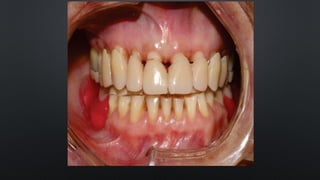

• AUSÊNCIA DENTÁRIA X BUSCA DE CONTATO

EXTRUSÃO

RELAÇÃO INTERDENTAL

• CONTATO OCLUSAL:DETERMINAÇÃO DA POSIÇÃO CERVICO-OCLUSAL RELAÇÃO INTERDENTAL

• AUSÊNCIA DENTÁRIAX BUSCA DE CONTATO EXTRUSÃO RELAÇÃO INTERDENTAL